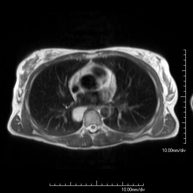

- Thorax

- Chest MRI

This non-invasive diagnostic procedure uses an electromagnetic field and radio waves (from a transmitter and receiver) to acquire high-definition anatomical images of the chest. It is a radiation-free procedure. It is indicated for lung lesions in which infiltration of the mediastinum or thoracic wall must be ruled out, to differentiate between solid and cystic chest lesions, etc. Sometimes paramagnetic contrast (gadolinium) must be used to complete the study.